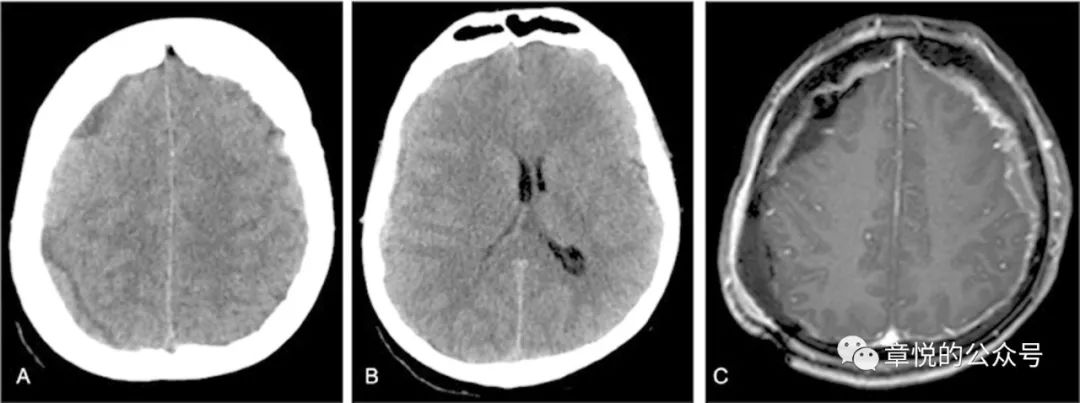

入院后予丙戊酸钠、左乙拉西坦和妥泰抗癫痫治疗,但住院3天患者依旧每天都有癫痫发作,表现为双眼向右侧视,头向右侧转,意识丧失,每次数分钟,发作间期意识模糊,萎靡不振,最多只能说出两三个字,行头颅MRI见左侧硬膜下血肿,并可见左侧颞枕叶肿胀,T2,FLAIR及DWI为略高信号。(图2)腰穿压力生化常规正常。

图2.FLAIR相左侧颞枕叶肿胀,信号增高

病人入院后癫痫频发,那会不会是癫痫后的表现呢?癫痫持续状态后出现磁共振异常表现的概率为11.6%,主要的改变有海马受累,胼胝体压部受累,皮层加丘脑受累,皮层受累和小脑交叉性失联络等(图8),影像改变能持续多长时间没有大宗报道,从小样本的研究看,部分病例在发病2周时仍旧有信号改变,这一点我们的案例倒是符合的。

图8 癫痫后脑磁共振异常的形态,海马受累,胼胝体压部受累,皮层加丘脑受累,皮层受累和小脑交叉性失联络等。(Milligan TA. et alFrequency and patterns of MRI abnormalities due to status epilepticus. Seizure- European Journal of Epilepsy , Volume 18 , Issue 2 , 104 – 108)

患者入院后,我们发现他的血糖十分高,空腹血糖11 mmol/L,餐后高达18 mmol/L,糖化血红蛋白超过11%,起初家属对我们提出的胰岛素治疗有点感冒,但连续3天患者情况不好于是就听从我们的意见,晚上一针下去,第二天早上血糖降到7 mmol/L,患者意识障碍明显好转,并且能够连词成句了,家属对此十万分的满意,毕竟是华山医院,一针见效!此后的几天,病人空腹血糖基本就控制6-7 mmol/L,餐后血糖8-9 mmol/L,病人情况一天好过一天,到第5天,家属感觉病人情况已经好了8-9成,查体患者对答切题,言语流利,计算力正常,虽然有时候找词有点困难,但已经不妨碍他正常表达了,接着DSA检查排除了血管畸形,复查头颅磁共振发现脑叶肿胀和异常信号消失。当出院时询问患者入院时的情况,他丝毫没有印象(图9)

图9 经过降糖治疗,脑叶肿胀和异常信号消失